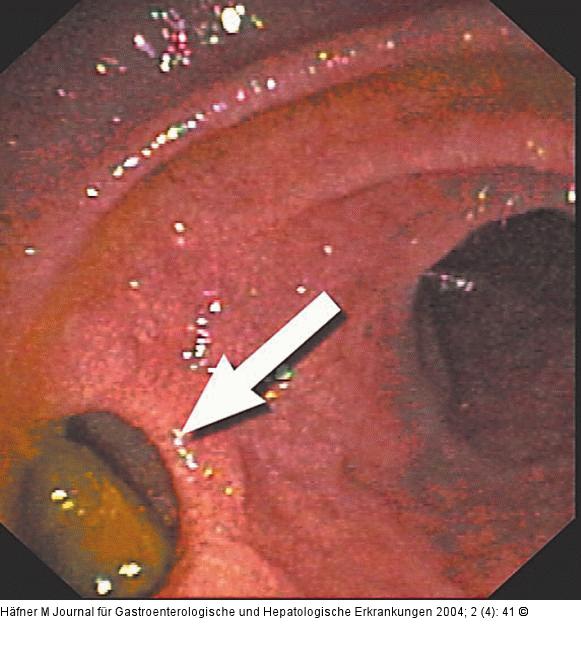

Endoskopie-Bilder-Quiz: Tubulovillöses Adenom

Journal für Gastroenterologische und Hepatologische Erkrankungen 2004; 2 (4)

: 41

Abbildung 1: Choledochoduodenostomie